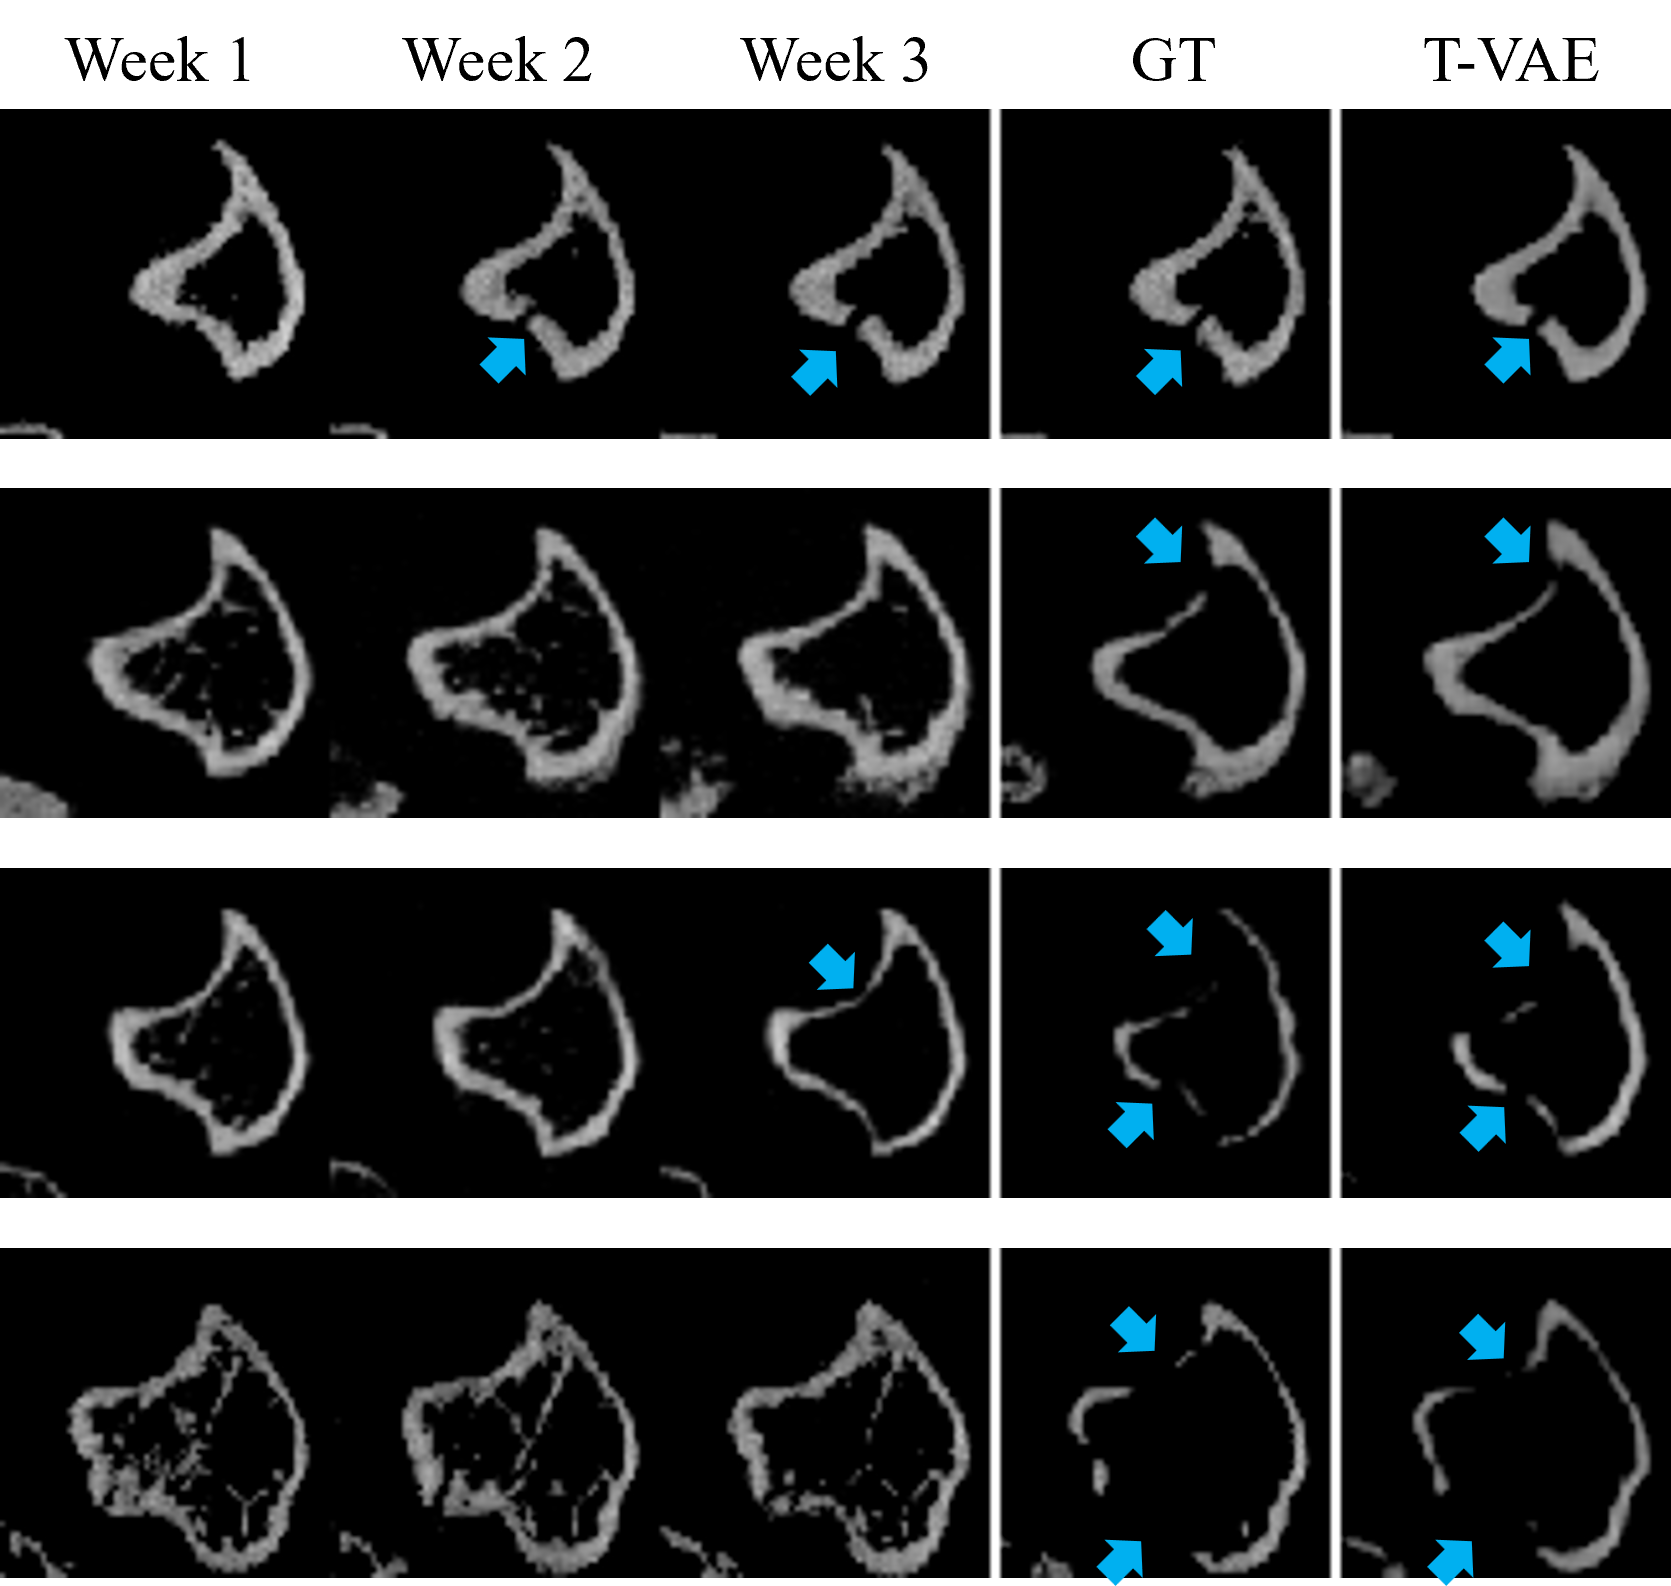

Refer to caption

Figure 1: Each row displays the first three weeks of bone CT slices (input), the ground truth image in week 4 and our predicted result in week 4. Blue arrows indicate osteolytic lesions.

The specific task in this work is that given the first three weeks of murine bone CT scans, we predict and generate CT scan images at the fourth week. Figure 1 shows the visualization of the input transverse/axial CT slices, the ground-truth CT slice at the fourth week and the generated CT slice by our Temporal VAE (T-VAE) model. Comparing our generated images with the ground-truth data, the visual results demonstrate that our model can predict the bone lesions accurately.

Figure 2: Each row displays the first three weeks of bone CT slices (input), followed with the predicted results from T-VAE (2D), C-LSTM, PredRNN, 3D-GAN, and ground truth image in week 4. Blue arrows indicate lesions in the ground-truth image or correct osteolytic lesion predictions. Red arrows indicate wrong lesion predictions. Please pay special attention to the boundary regions of the bone (i.e., the tibial cortical bone), which are the primary regions to determine whether their is lesion or not. Qualitatively, our model T-VAE provides the best results among all the models.

Qualitative Comparison. Figure 2 shows the visual results generated by different prediction models. In Figure 2, there is no lesion in the slices of the first three weeks but lesion may occur in the fourth week. This makes the prediction very challenging. On such cases, all the compared models fail to make accurate bone lesion predictions. In contrast, our model is able to capture subtle temporal progression patterns in the first three weeks and predict the state of the bone image in the fourth week accurately. Notably, 3D-GAN makes a few correct lesion predictions. However, it tends to over-predict the lesion, i.e., the lesion region is much larger than the ground-truth lesion or lesion is predicted but there is no lesion in the ground-truth.